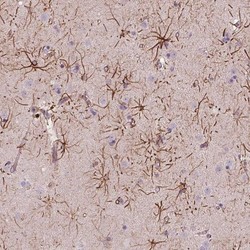

Immunohistochemistry

NBP1-81590 IHC